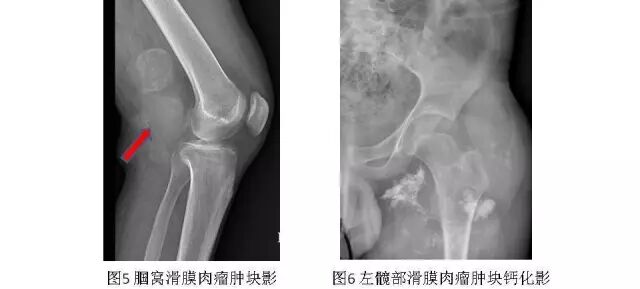

1.X线平片

软组织肿块、肿瘤钙化及局部骨质破坏是滑膜肉瘤的基本X线表现。其中软组织肿块密度相对较高,有的其内可见钙化影(图5、图6)。